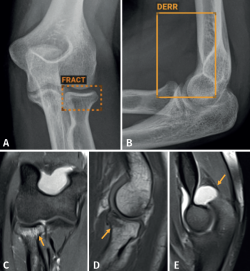

Aunque no hemos realizado un estudio de sensibilidad y especificidad por la complejidad que entraña en la práctica asistencial, consideramos que los resultados son satisfactorios, en línea con lo publicado en la literatura científica. Destacamos la eficacia del algoritmo en la detección de pequeñas fracturas arrancamiento (Figura 3), fracturas de radio distal y proximal (Figura 4), y fracturas múltiples (Figura 5).

retla.08115.fs2402001-figura4.png

Figura 4. Fractura de radio proximal: radiografía (Rx) de codo anteroposterior (AP) (A) y lateral (B) y resonancia magnética (RM) coronal T2 con supresión grasa (C), sagital T1 (D) y sagital T2 con supresión grasa (E). La inteligencia artificial (IA) identifica en la Rx de codo una dudosa fractura de la cabeza del radio (A) y un derrame articular (B). Ambos hallazgos son confirmados por la RM, que identifica la fractura en la cabeza del radio (C y D) y el derrame articular (E).

Figura 4. Fractura de radio proximal: radiografía (Rx) de codo anteroposterior (AP) (A) y lateral (B) y resonancia magnética (RM) coronal T2 con supresión grasa (C), sagital T1 (D) y sagital T2 con supresión grasa (E). La inteligencia artificial (IA) identifica en la Rx de codo una dudosa fractura de la cabeza del radio (A) y un derrame articular (B). Ambos hallazgos son confirmados por la RM, que identifica la fractura en la cabeza del radio (C y D) y el derrame articular (E).